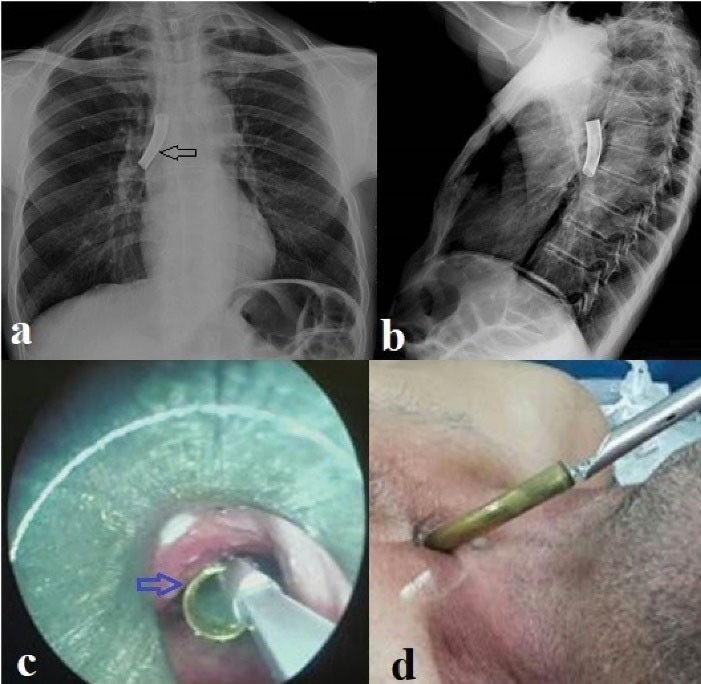

Foreign bodies were evaluated in terms of location as follows: 11 foreign bodies (42.4%) were in the trachea, 9 (34.6%) in the right main bronchus and 6 (23%) in the left main bronchus. Foreign bodies types were as follows: Vocal prosthesis in 10 (38.5%) cases, tracheostomy tube in 4 (15.4%) cases (Figure 1), cleaning brush in 4 (15.4%) cases (Figure 2), aspiration catheter in 2 (7.7%) cases, plastic plug in 2 (7.7%) cases, pencil cap in 2 (7.7%) cases, tweezers in 1 (3.8%) case (Figure 3) and plastic rod in 1 (3.8%) case.

Figure 1.

Removal of a patient who aspirated the tracheostomy cannula with a rigid bronchoscope. (a) Posterior-Anterior (PA) chest x-ray; black arrow shows the tracheostomy cannula in the right main bronchus. (b) View of the tracheostomy cannula on lateral chest radiography. (c and d) Rigidbronchoscopy, blue arrow indicates intraoperative tracheostomy cannula.